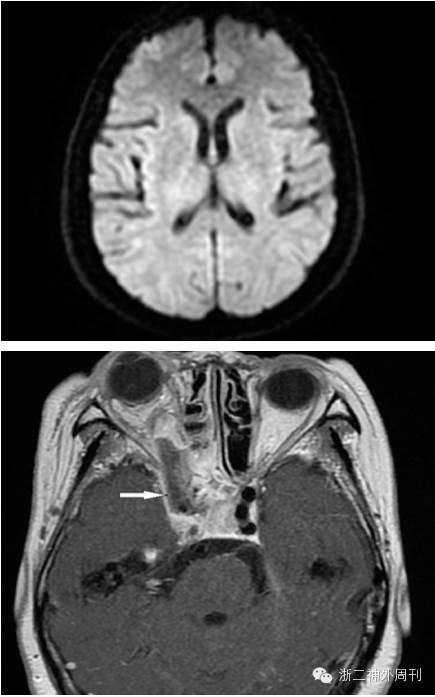

术后予抗凝、扩容等处理,患者病情平稳,次日头颅MRI+DWI复查,未见明显梗塞灶,但异物残留明显(图8)。

图8. 闭塞后DWI检查未见缺血梗塞发生,异物残留明显。